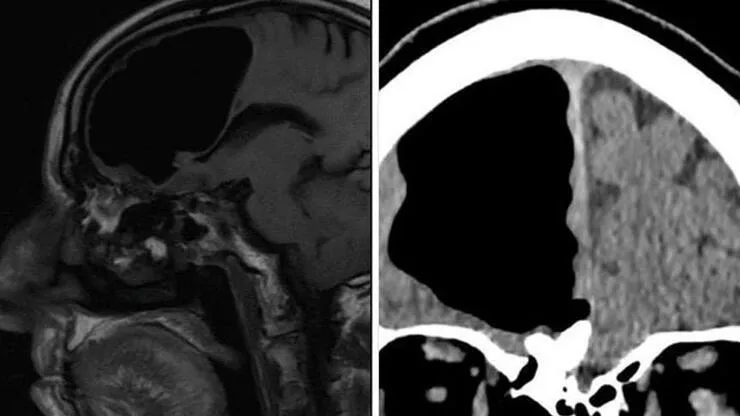

29 Mayıs 2023 Pazartesi 21:19Sadece başı ağrıyordu Mirror’ın haberine göre; Doktorlar, şiddetli baş ağrıları yaşayan kadının beyninde büyüyen bir tenya larvası buldular. Yadira Rost, şiddetli baş ağrılarıyla 9 ay önce tanıştı. Ve iyice şiddetlenen ve daha da kötüleşen bu ağrılar nedeniyle tıbbi yardım almaya karar verdi.Beyninde kurt larvası olduğu belirlenen kadın ameliyata alındı. 31 yaşındaki kadın şimdi 2 yıl önce yaptığı Meksika gezisinde hastalık kaptığına inanıyor. Meksika’da dışkı ile kontamine gıdaların yaygınlığı biliniyor. Ama çoğu insan bunu bir kaç gün içinde atlatıyor. Ancak Yadira için maalesef ki bu durum kolay olmadı ve larva beynine yerleşip, orada büyümeye devam etti. Haberimizin devamını okumak için Lütfen sonraki sayfaya geçiniz..